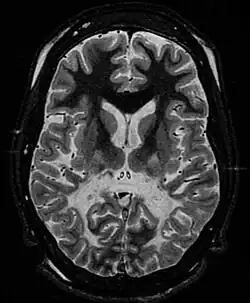

| White matter, with reduced volume and increased signal intensity. The anterior white matter is spared. Features are consistent with X-linked adrenoleukodystrophy. | |